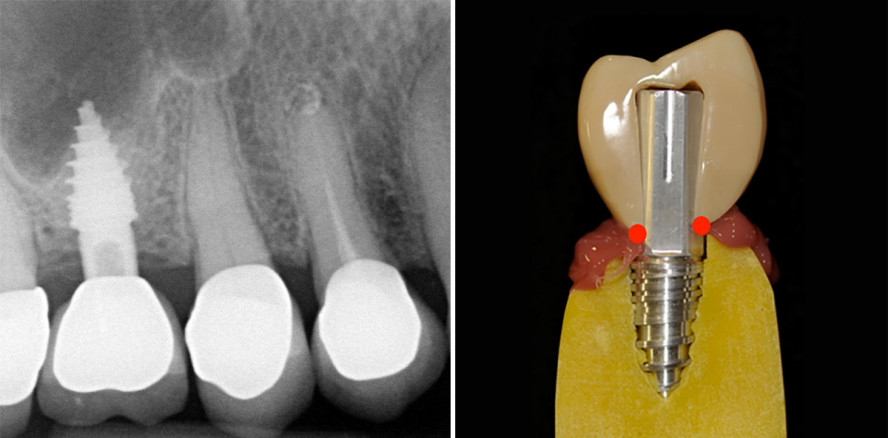

Die retrospektiven, röntgenologischen und klinischen Nachuntersuchungen des Verfassers, die dieser im Rahmen seiner Praxistätigkeit anhand der in den letzten zehn Jahren flapless inserierten, einteiligen Implantate durchführen konnte, bestätigen die oben genannten Vorteile und deren Langzeiterfolg (Abb. 1 und 2).

Das verwendete einteilige Implantatsystem hat systembedingt keine Implantat-Abutment-Verbindung, sodass es zweiteiligen Implantaten hinsichtlich mechanischer Stabilität und Bakteriendichtigkeit deutlich überlegen ist.4 Diese Problematik des Microleakage beschreiben auch ausgewählte Dissertationen (Abb. 8a und b).12, 13 Der fehlende Mikrospalt, die fehlende Mikrobewegung sowie das immer sterile Abutment reduzieren das Risiko von Periimplantits und vermeiden Schraubenlockerungen, Abutmentlockerungen beziehungsweise -brüche und Implan-tatbrüche (Abb. 9).

Zementierte einteilige Implantatversorgungen stellen ein Konzept für den Langzeiterfolg in der Implantologie dar. Die umfassende Analyse evidenzbasierter klinischer Studien bezüglich einteiliger Implantate bestätigt das Ergebnis des Knochenverlaufes um einteilige Implantate auf den gezeigten Röntgenbildern.